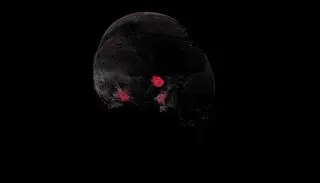

Badanie tomografii komputerowej czaszki

Po analizie uszkodzeń kości biegli chcą ustalić, jak zginęli żołnierze na Westerplatte

W trakcie prac biegli zbadali wszystkie znalezione kości. Stwierdzone zmiany dokładnie opisali i sfotografowali. Biegły radiolog zlecił i wykonał badania tomografii komputerowej wybranych elementów szkieletów, żeby zweryfikować uszkodzenia.

Instytut Pamięci Narodowej w Gdańsku przesłał do mediów również film, na którym zilustrowano wyłamanie około połowy kości pokrywających część mózgową czaszki i większość kości części twarzowej czaszki. Strzałkami i czerwonym kolorem na kolejnych zdjęciach zaznaczone są odłamki metalu wbite w kości czaszki.